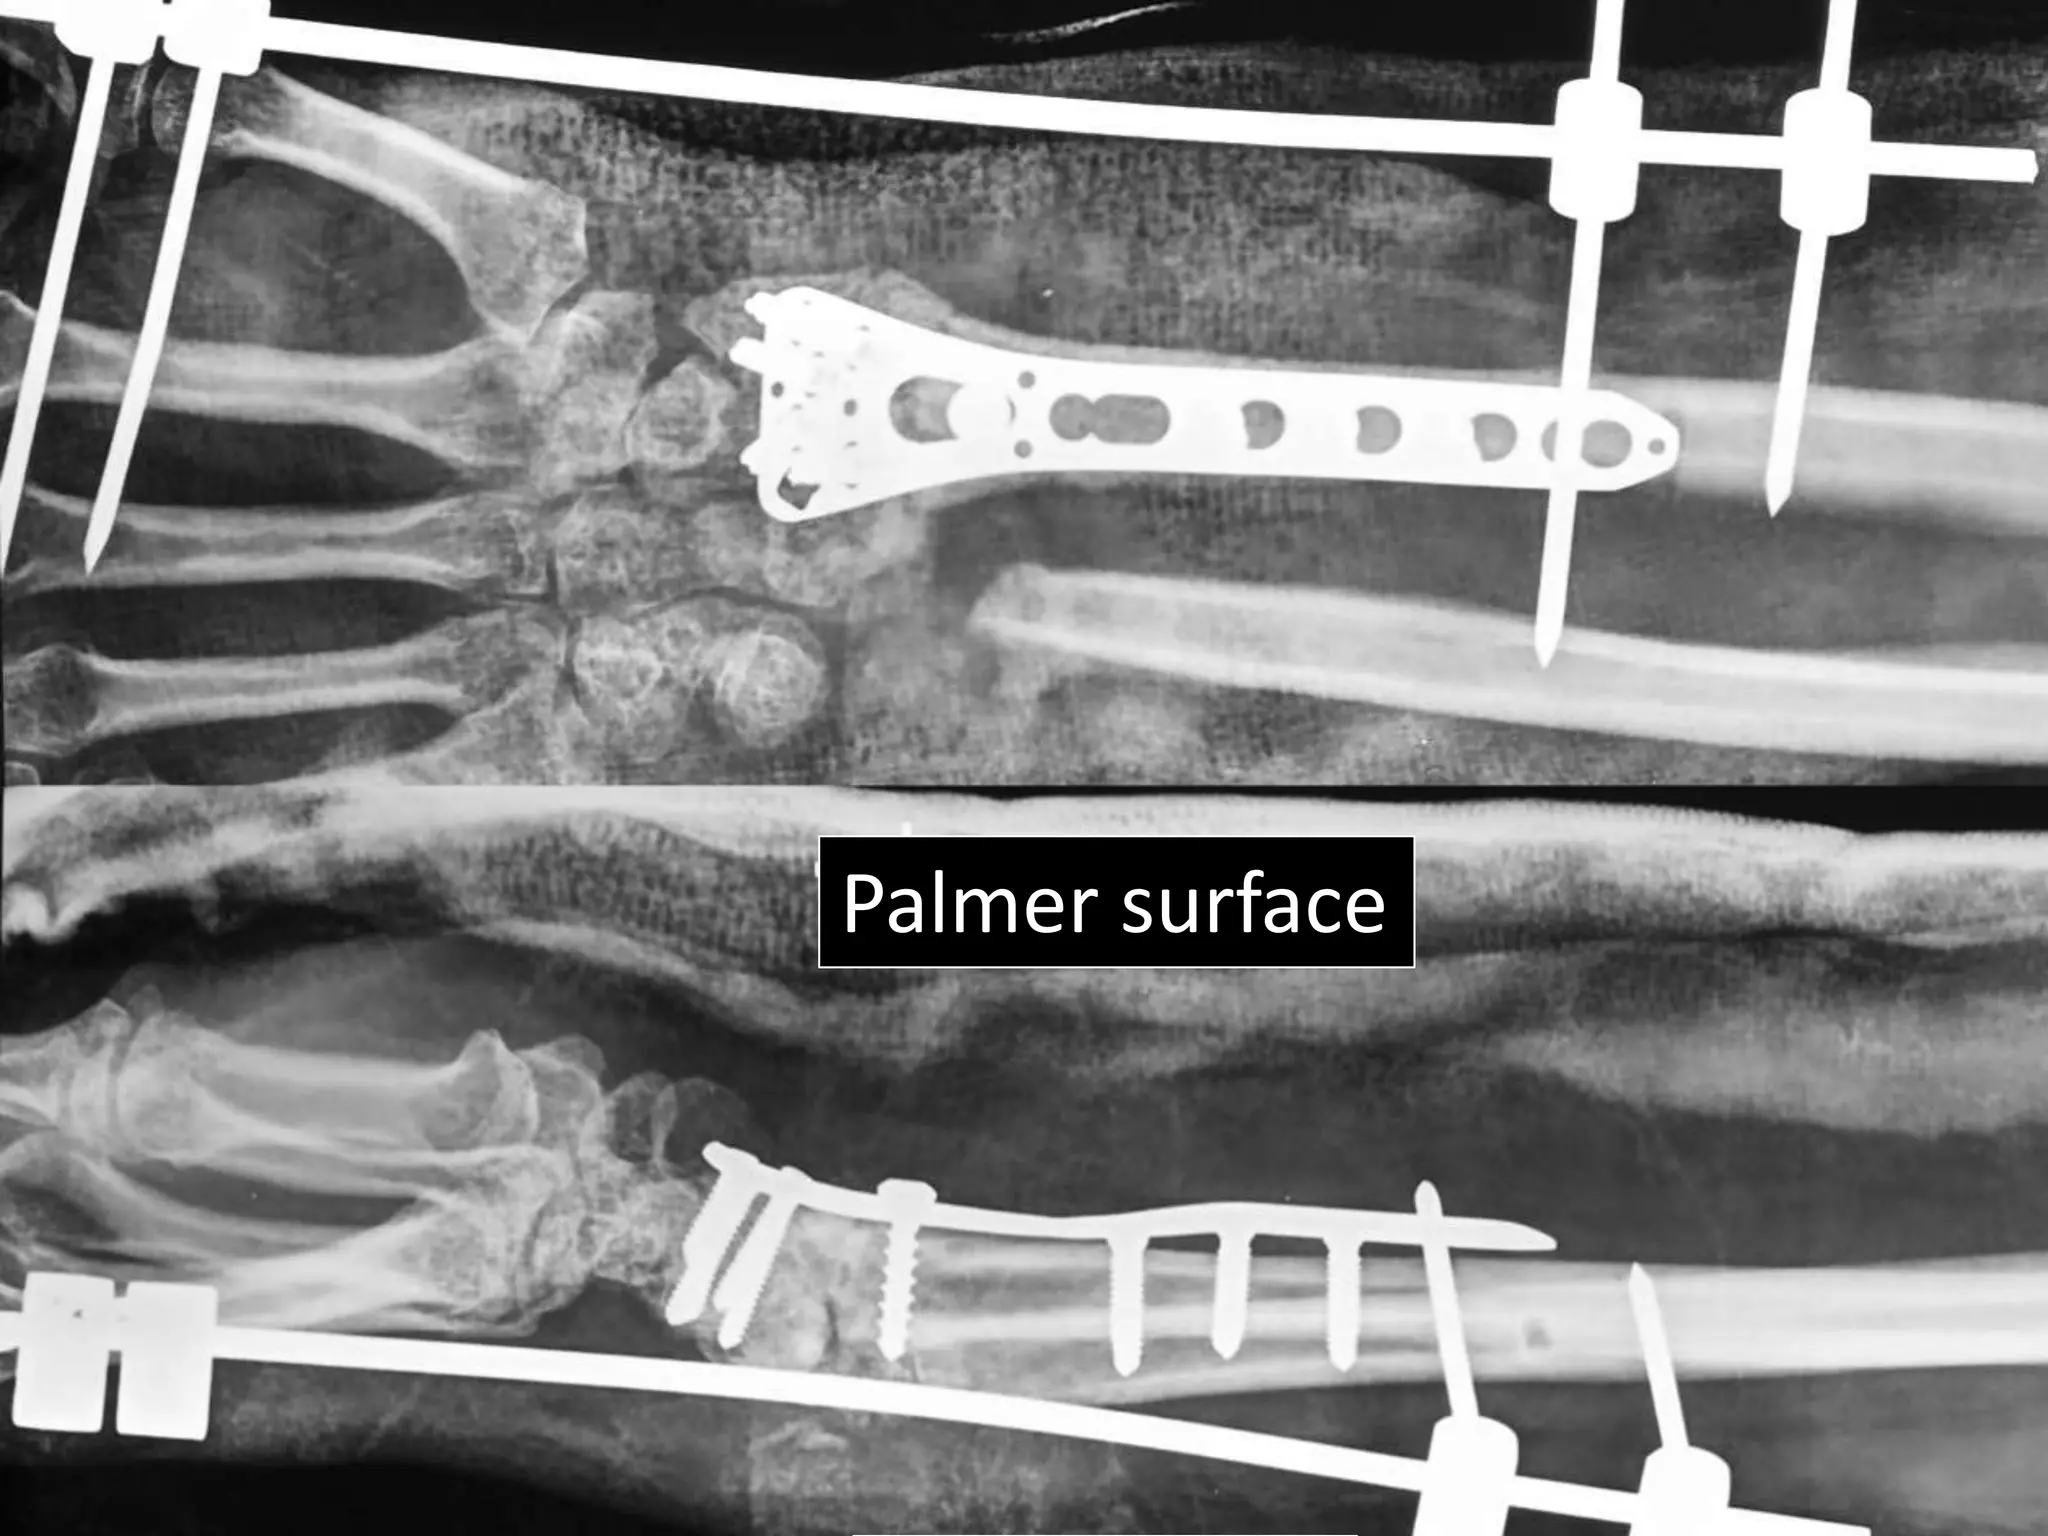

Severe Palmer flexion and ulnar deviation deformity

Dorsal

Palmer/voral

Ulnar Radial

Palmer surface